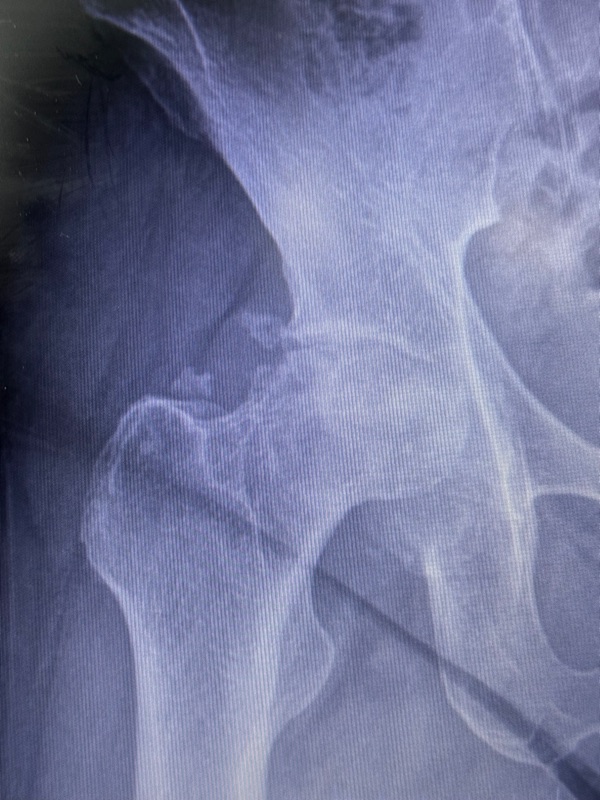

คุณเคยปวดสะโพกเรื้อรัง เดินแล้วเจ็บ หรือขยับข้อสะโพกแล้วติดขัดหรือไม่? อาการเหล่านี้อาจไม่ใช่แค่ “ปวดเมื่อยธรรมดา” แต่อาจเป็นสัญญาณของ โรคหัวสะโพกขาดเลือดไปเลี้ยง (Avascular Necrosis of the Femoral Head - AVN) ซึ่งเป็นภาวะที่อาจนำไปสู่กระดูกสะโพกทรุดตัวและข้อสะโพกเสื่อมได้!

โรคนี้เกิดจาก การไหลเวียนของเลือดไปยังหัวกระดูกสะโพกลดลงหรือถูกตัดขาด ส่งผลให้เซลล์กระดูกตายในบริเวณนั้น และเมื่อเวลาผ่านไป กระดูกจะอ่อนแอ ทรุดตัว และเกิดข้อสะโพกเสื่อม

หากคุณมีอาการเหล่านี้ อย่าปล่อยไว้จนรุนแรง! ควรพบแพทย์เพื่อตรวจวินิจฉัย ซึ่งอาจใช้ เอกซเรย์ (X-ray) หรือ MRI เพื่อดูความเสียหายของกระดูก